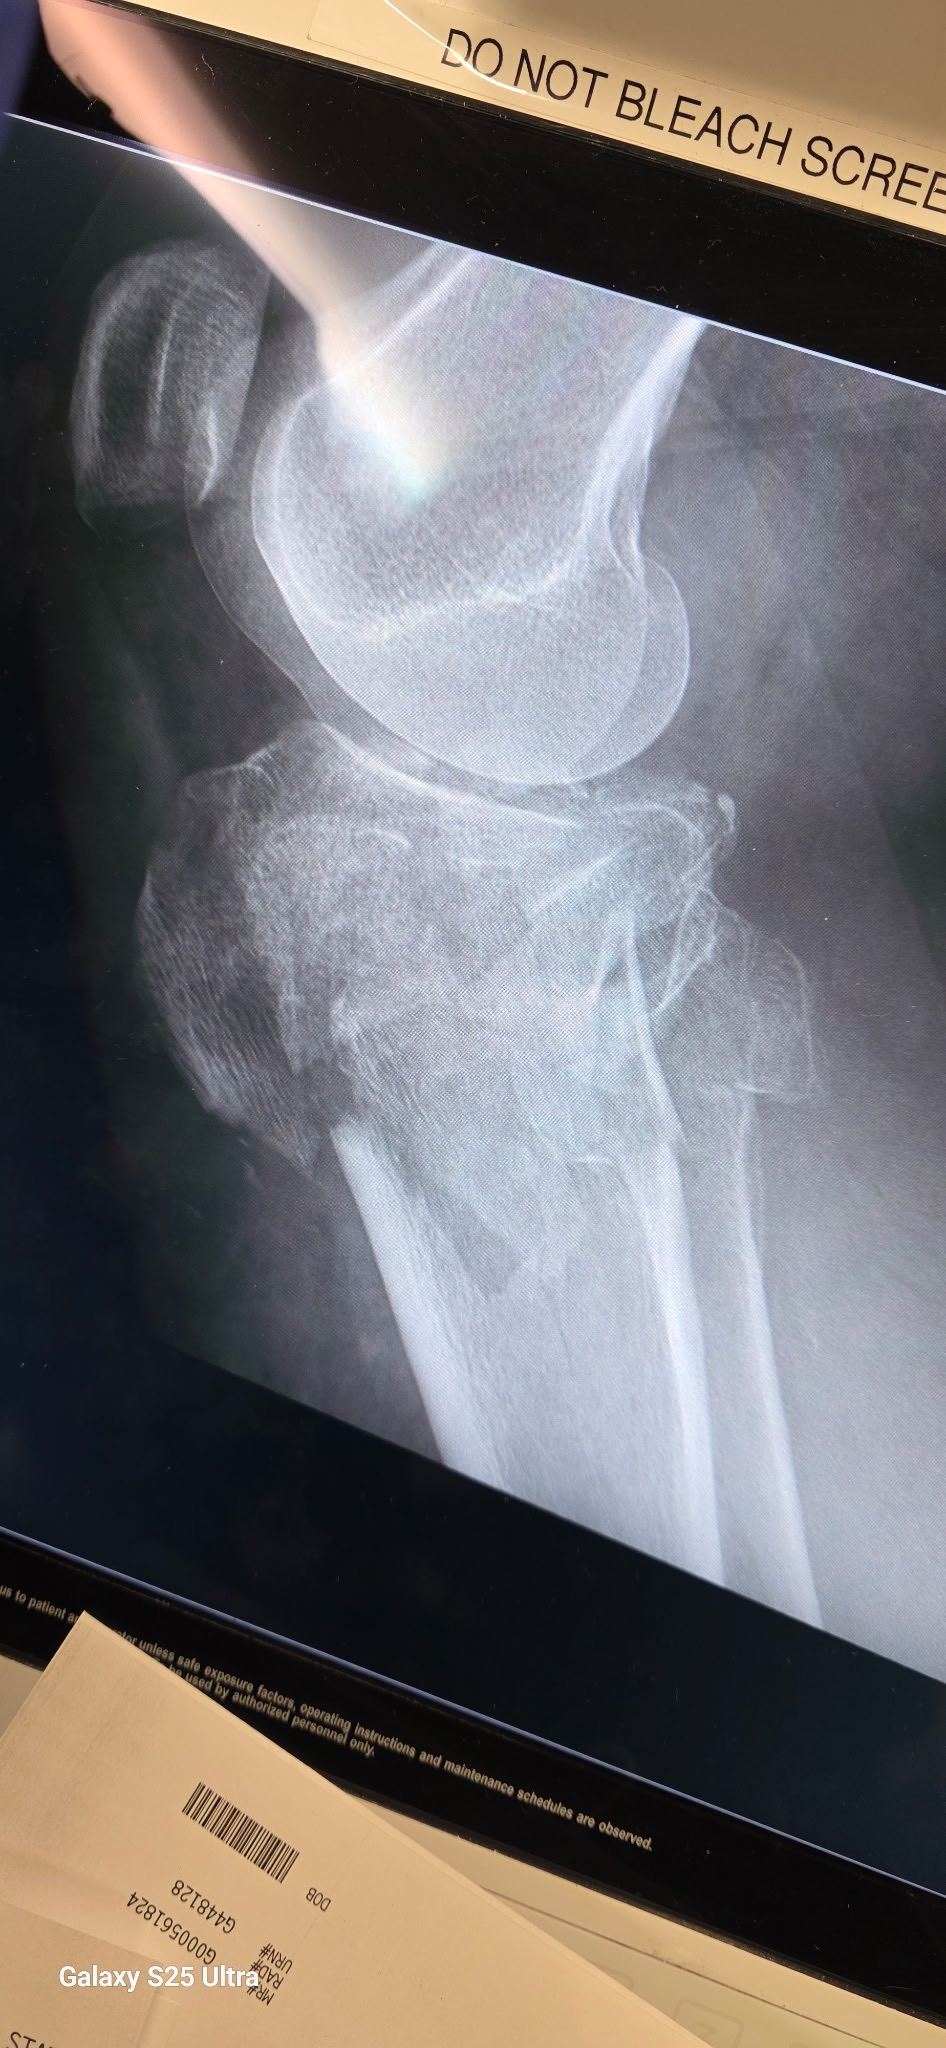

Joan, my sister, traveled to Florida to help her daughter by babysitting her grandchildren while her daughter attended a Navy event in Washington. Just before Christmas, while the children were at school, Joan decided to retrieve some Christmas decorations from a ladder. Unfortunately, she fell and suffered a severe injury just below her left knee cap. In pain and unable to walk, she managed to crawl inside and call for help. She was taken to the hospital, where doctors discovered a complex fracture and significant swelling. Due to the severity of her injury, she required an external fixator and multiple surgeries, including procedures to address infection after a culture showed infection in her leg, and to remove blood from her leg. The surgeon milked a lot of blood from her leg during one of the procedures.